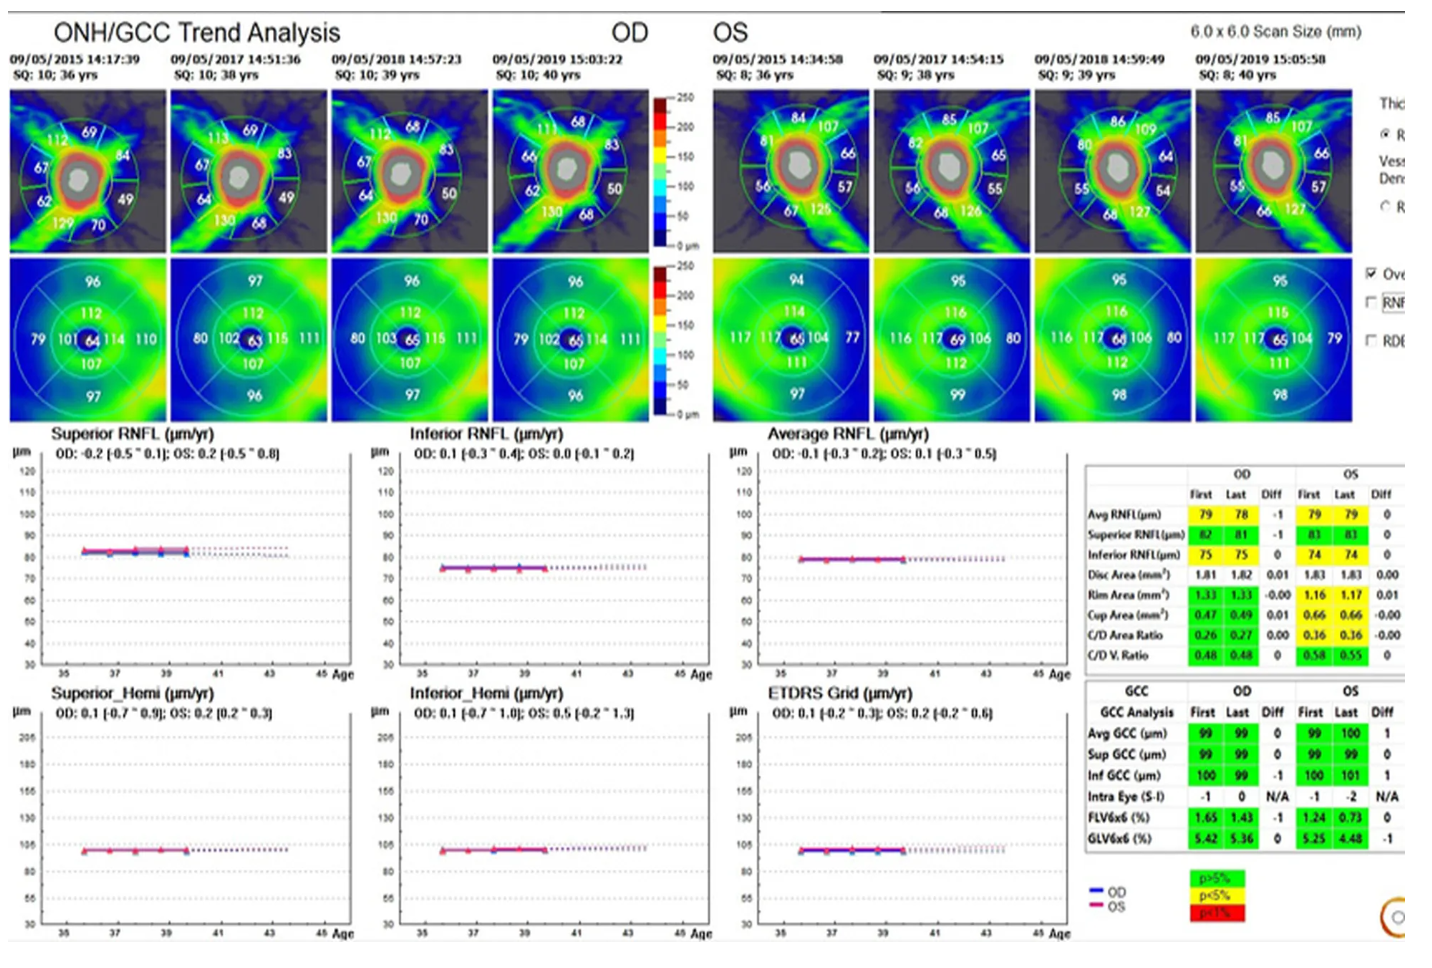

Оптический когерентный томограф Optovue Solix обладает повышенной скоростью сканирования — 120 000 А-сканов в секунду. SOLIX предоставляет множество инструментов для нового поколения борьбы с заболеваниями, которые повышают пропускную способность и обеспечивают превосходный уход за пациентами. В отличие от томографов более ранних поколений ОКТ SOLIX OPTOVUЕ может определять наличие конкрементов и новообразований сосудов сетчатки и хориоидеи, позволяет получать максимально точную послойную визуализацию структур глаза.

- Программа AngioAnaliticsTM для количественного анализа сосудов сетчатки;